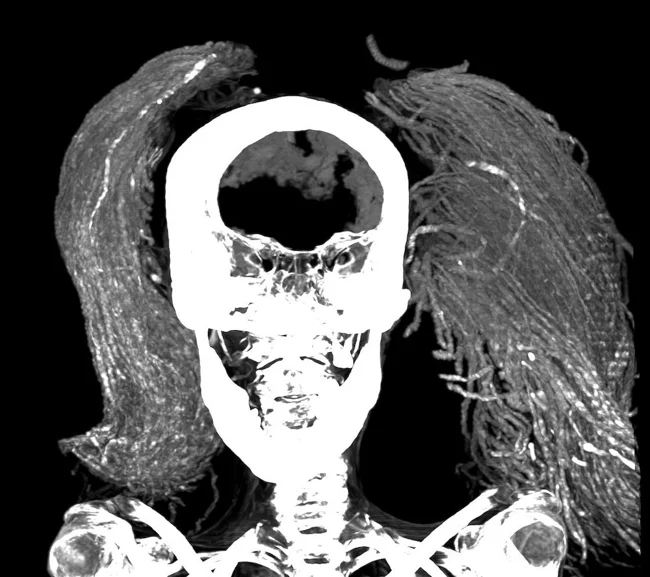

Researchers have used cutting-edge scientific methods to study the mummy and learn details about her life and death.

The woman was missing several teeth (she probably lost them before her death), and her height was about 1.54 m. According to CT scans, she was about 48 years old at the time of her death and suffered from arthritis.

The mummy's brain, diaphragm, heart, lungs, liver, spleen, kidneys and intestines were preserved inside. This came as a surprise, since the classic method of embalming in the New Kingdom (550-1069 BCE) involved removing all of these organs except the heart. ![]()